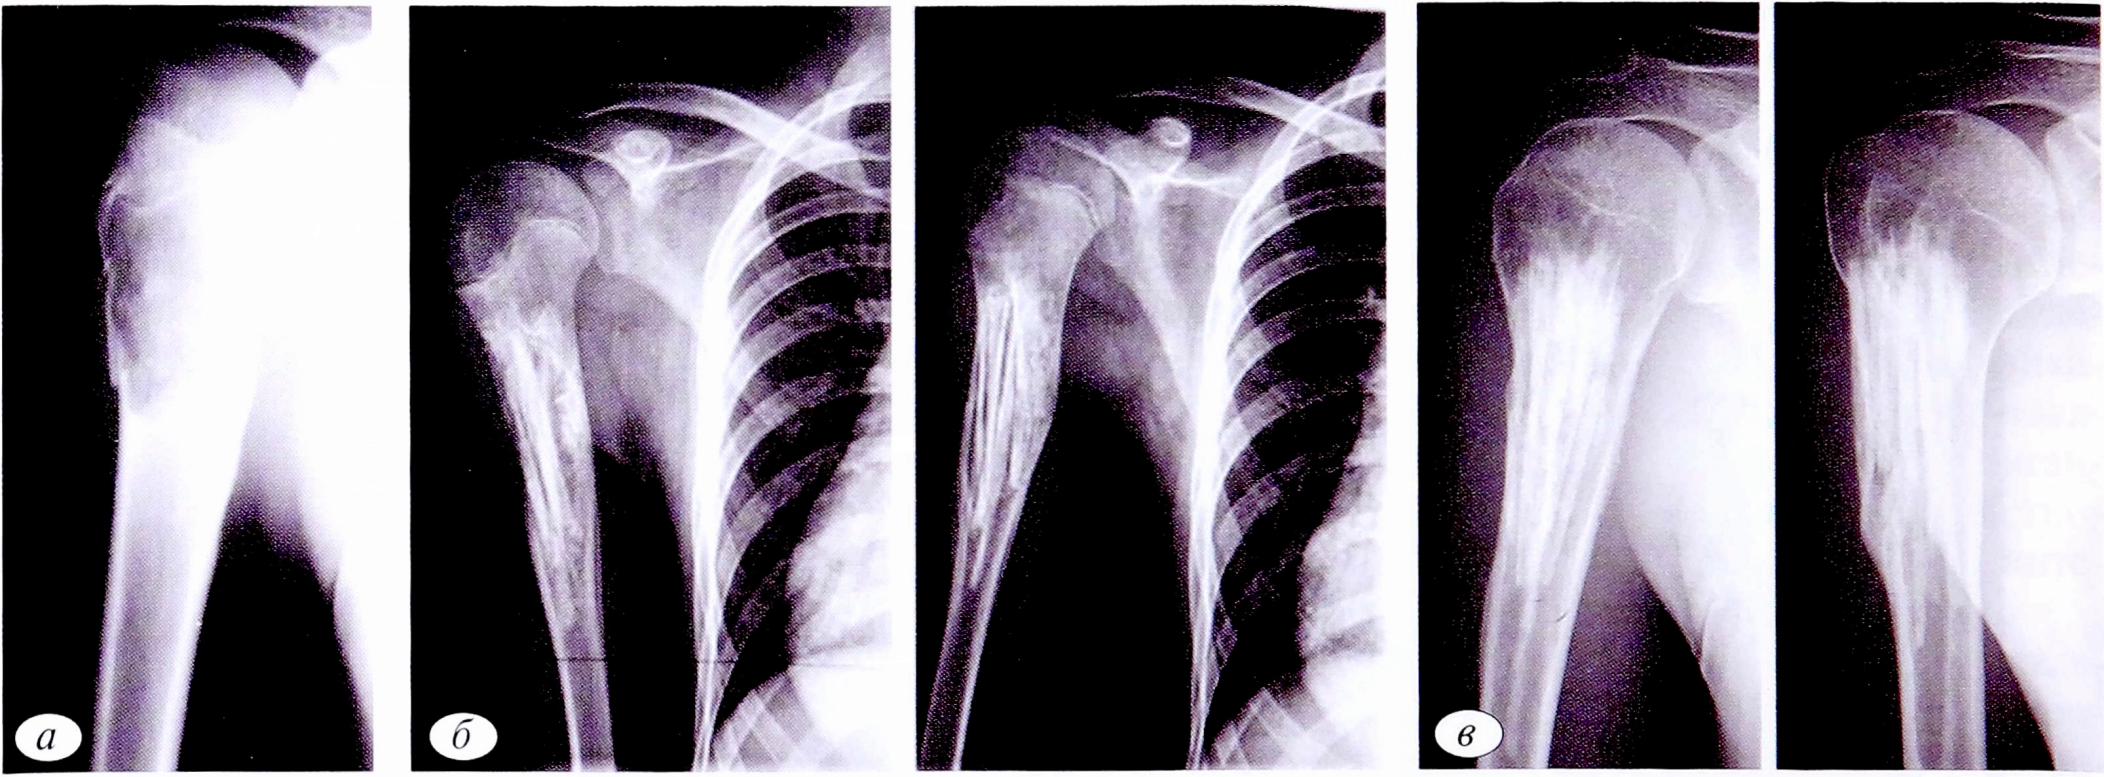

При болезни Олье основные клинические проявления (деформация и укорочение пораженных сегментов скелета) возникают достаточно рано — в возрасте от 2 до 10 лет. Несмотря на то что заболевание диагностировалось в раннем возрасте и больные получали соответствующее оперативное лечение, эта категория пациентов оставалась в зоне риска возникновения патологических переломов, которые имели место в 6 случаях: 4 без смещения,2 со смещением. При лечении пациентов проводилась краевая резекция кости с удалением патологического очага в пределах здоровой ткани и последующим замещением дефекта трансплантатами. Остеосинтез перелома выполнялся металлоконструкцией (рис. 8).

Рис. 8. Пациент И.,15 лет. Диагноз: патологический перелом средней трети левой плечевой кости на фоне болезни Олье. Рентгенограммы левой плечевой кости: а — до операции; б — после операции: открытая репозиция, краевая резекция нижней и средней третей левой плечевой кости, аллопластика, металлоостеосинтез.

Fig. 8. Patient /.,15 years old. Diagnosis: pathological fracture of the middle third of the left humerus due to Ollier disease. a — radiographs of the left humerus before surgery; б — radiographs of the left humerus after surgery: open reduction, marginal resection of the lower and middle third of the left humerus, alloplasty, metallosteosynthesis.